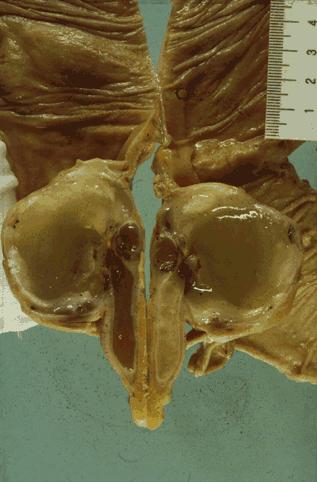

Relatively typical mucinous cystadenocarcinoma of the appendix (malignant mucocele)

Appendix/Mucinous cystadenocarcinoma

Large intestine(Colon)/Appendix

Macro.

40 -